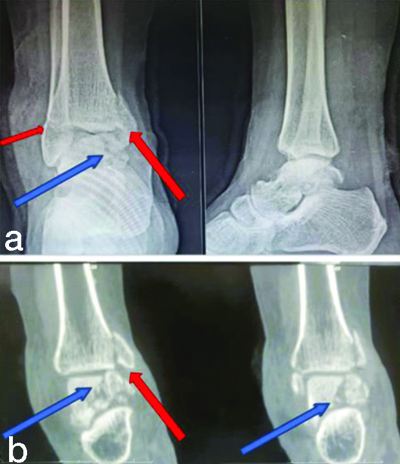

Radiographs revealed a displaced vertical fracture of the body of the talus, a vertical fracture of the medial malleolus and a transverse fracture of the lateral malleolus [Table/Fig-2]. There was no past medical or surgical history, nor any previous surgeries. A preanaesthetic evaluation was conducted and fitness was given as American Society of Anaesthesiologists (ASA) grade 1. The patient was planned for open surgical fixation of the ankle.

a) Anteroposterior (AP) and lateral radiographs of ankle; and b) Computed tomography coronal section of ankle showing fracture pattern. {Blue arrow showing talus fracture, Red arrow showing medial (large) and lateral (small) malleolus}.